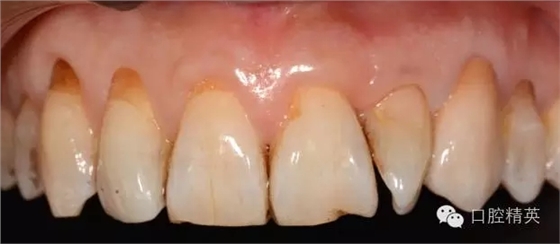

圖123口內(nèi)修復(fù)前情況:殘根位于齦上3MM,牙周無(wú)紅腫.

口內(nèi)檢查: 23殘根,位于齦上3MM,根管口探無(wú)反應(yīng),叩(+-),無(wú)松動(dòng),牙周無(wú)紅腫.X片示:23根管無(wú)阻射,根尖骨密度降低.

11.12.13頸部楔形缺損,探敏感,牙髓活力正常.

全口牙結(jié)石色素(+).